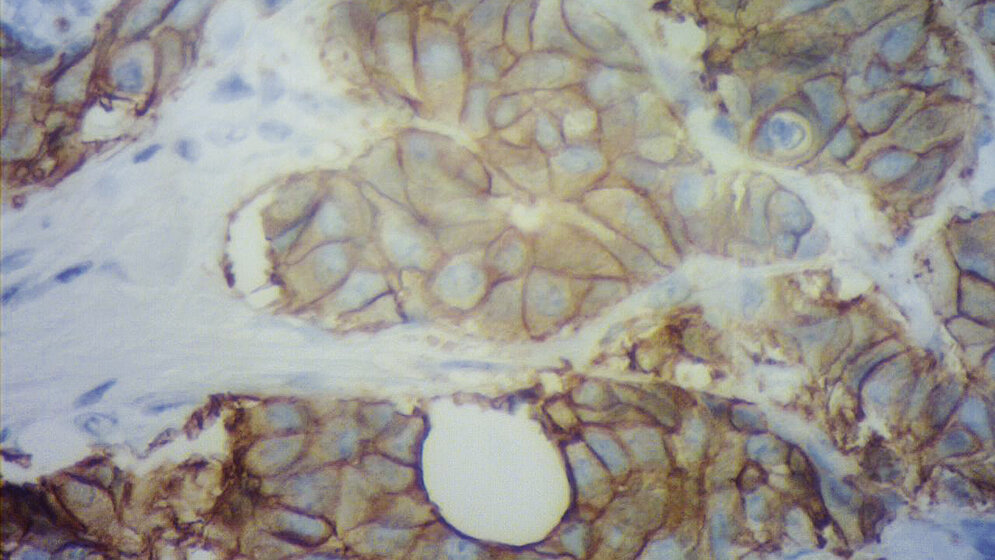

Die Immunhistochemie ist heute aus der Routine der Pathologie nicht mehr wegzudenken. Seit Beginn gab es weitreichende Entwicklungen in diesem Bereich. Immer mehr nimmt die IHC im Bereich der Diagnostik an Bedeutung zu, gerade auch bei der Prognose und Therapieentscheidung bei Tumoren. Deshalb ist eine Standardisierung enorm wichtig, um die gleichbleibende Qualität zu sichern. Validierung und Verifizierung sollten deshalb zum täglichen Laboralltag gehören. Auch die Teilnahme an Ringversuchen sollte heute als externe Qualitätssicherungsmaßnahme zur Laborroutine gezählt werden. Die IHC spielt mittlerweile beim Einsatz in der Differenzialdiagnose bei Tumorerkrankungen eine tragende Rolle.